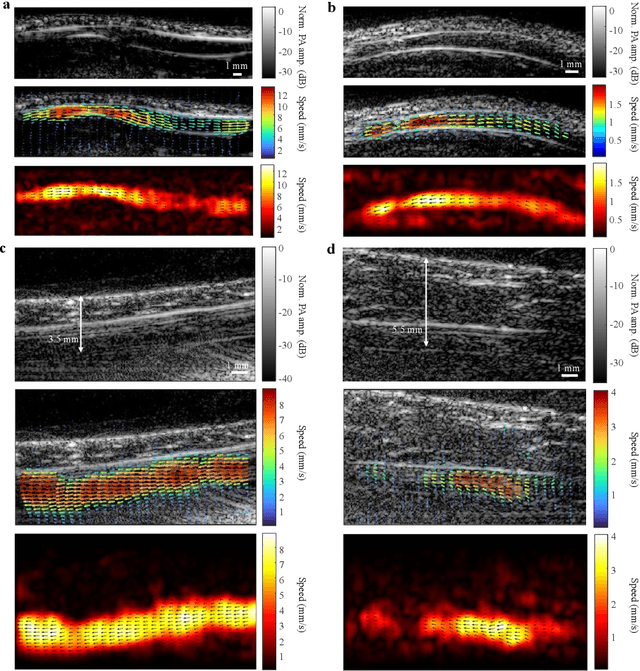

Abstract:Non-invasive imaging of deep blood vessels for mapping hemodynamics remains an open quest in biomedical optical imaging. Although pure optical imaging techniques offer rich optical contrast of blood and have been reported to measure blood flow, they are generally limited to surface imaging within the optical diffusion limit of about one millimeter. Herein, we present photoacoustic vector tomography (PAVT), breaking through the optical diffusion limit to image deep blood flow with speed and direction quantification. PAVT synergizes the spatial heterogeneity of blood and the photoacoustic contrast; it compiles successive single-shot, wide-field photoacoustic images to directly visualize the frame-to-frame propagation of the blood with pixel-wise flow velocity estimation. We demonstrated in vivo that PAVT allows hemodynamic quantification of deep blood vessels at five times the optical diffusion limit (more than five millimeters), leading to vector mapping of blood flow in humans. By offering the capability for deep hemodynamic imaging with optical contrast, PAVT may become a powerful tool for monitoring and diagnosing vascular diseases and mapping circulatory system function.